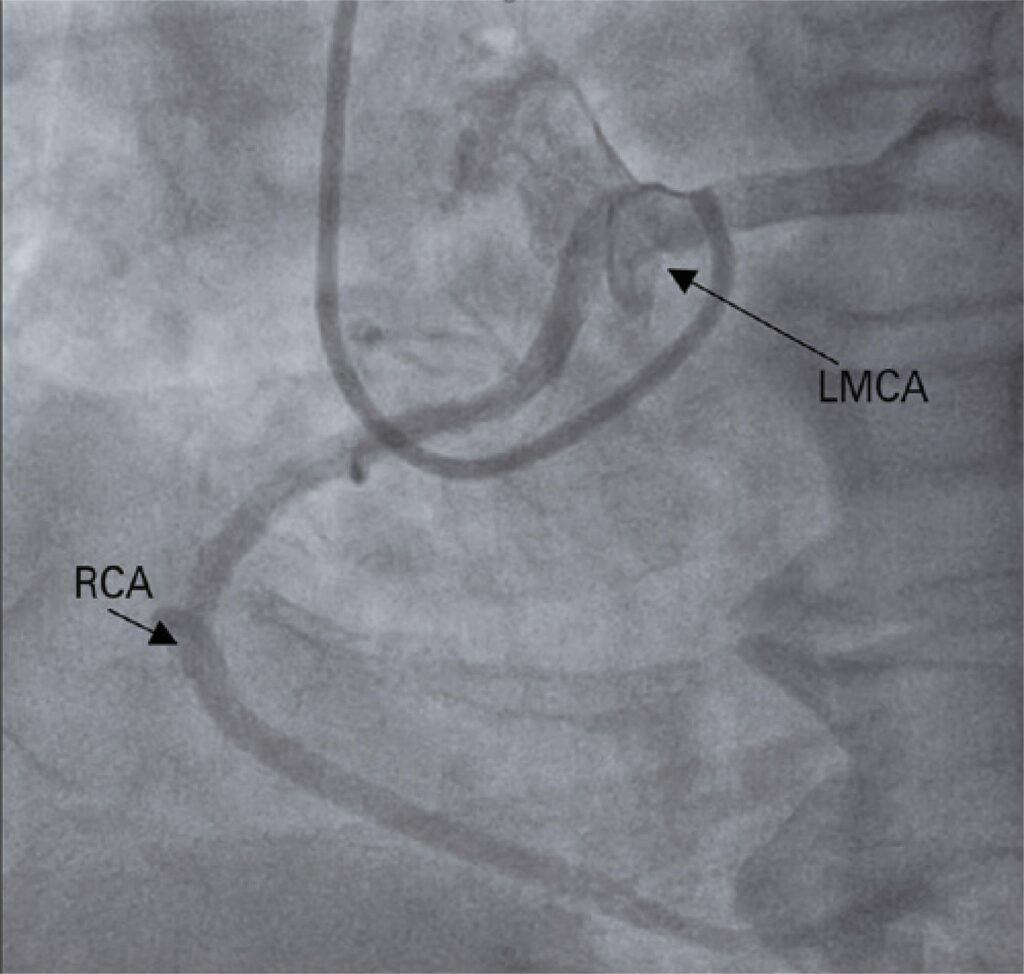

Coronary anomalies are less frequent than acquired coronary diseases, such as atherosclerosis, and have been implicated as a cause of cardiovascular events. This case report describes an incidental finding on angiography of an anomalous right coronary artery with origin in the left coronary sinus and an intra-arterial course, after an episode of aborted sudden death. The Heart Team analysis indicated a percutaneous approach with drug-eluting stent implantation at the origin of the right coronary artery as the best treatment, and the procedure was successfully performed. This case report and recent studies have demonstrated percutaneous treatment of coronary anomalies is a safe option for selected patients, considering clinical presentation, anatomy study, and training of the cath lab team.